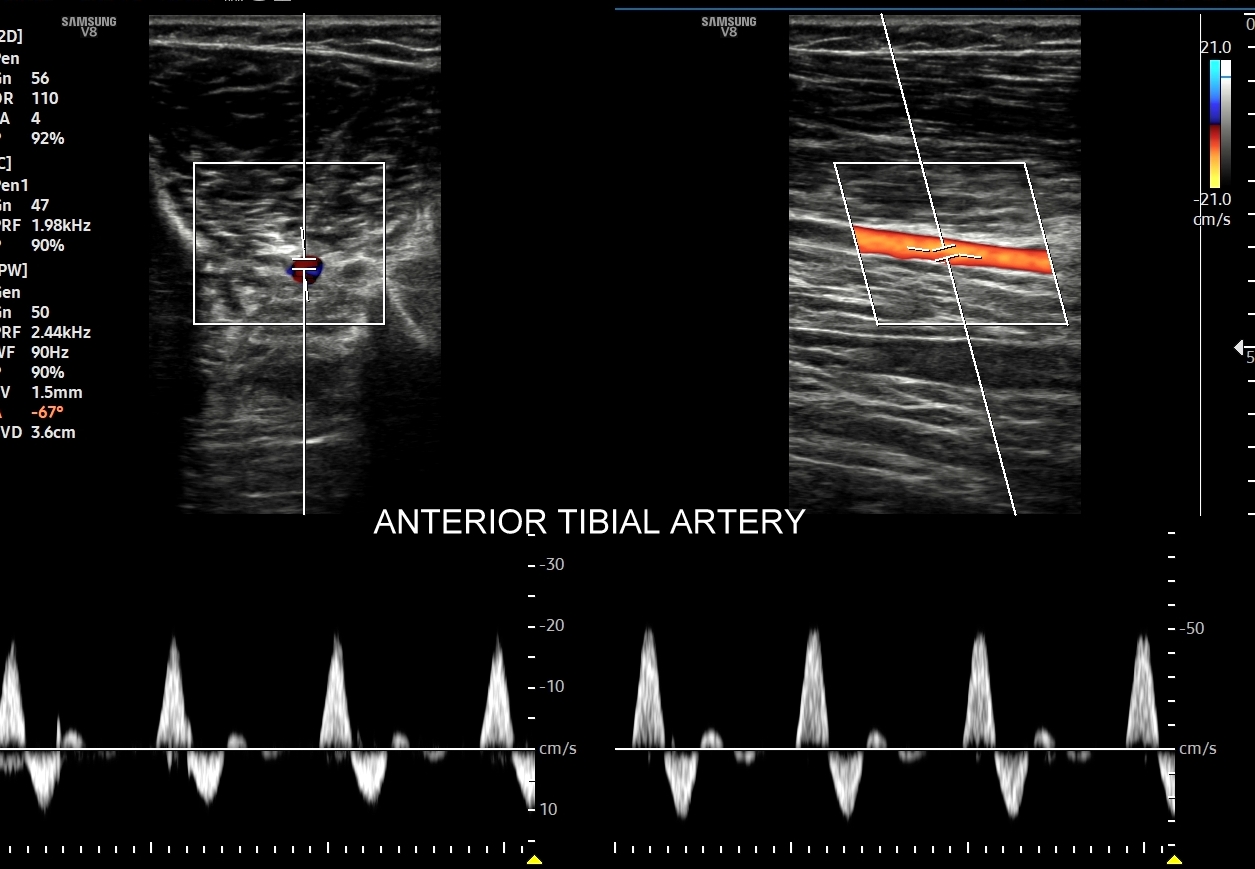

- Z kolei profile o wysokiej pulsacyjności charakteryzują się tym, iż posiadają wąskie i ostre piki skurczowe, a w fazie rozkurczowej odwrócone lub/i nieobecne przepływy. Profile tego typu występują w tętnicach unaczyniających kończyny.

W przypadku tętnic podążających do kończyn w warunkach spoczynkowych obserwuje się charakterystyczne wielozałamkowe profile przepływów zawierające od 2 do nawet 4 następujących po sobie przeciwstawnych załamków o zmniejszającej się amplitudzie, przy czym w tętnicach tych zwykle nie obserwuje się ciągłego przepływu w fazie rozkurczowej. Stały lub prawie stały przepływ rozkurczowy, tj. przepływ o pośredniej pulsacyjności, może pojawić się w tętnicach kończyn w trakcie intensywnego wysiłku fizycznego.